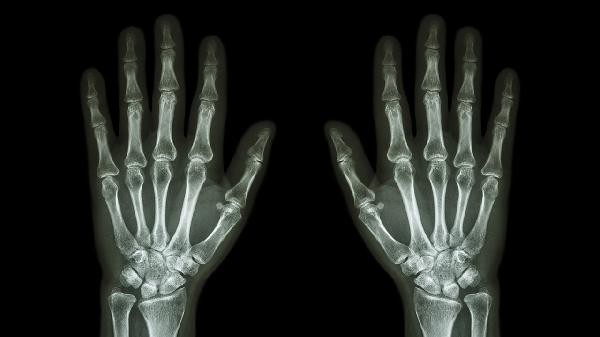

骨关节炎多见于中老年人,与关节软骨退行性变有关。手指关节弯曲时可能出现疼痛、僵硬感,晨起时症状明显,活动后稍缓解。X线检查可见关节间隙狭窄或骨赘形成。治疗可遵医嘱使用硫酸氨基葡萄糖胶囊、双醋瑞因胶囊等软骨保护剂,配合局部热敷缓解症状。

手指关节扭伤、骨折或脱位后未完全恢复时,弯曲活动可能引发疼痛。需通过X线或MRI明确损伤程度,急性期应制动冰敷,后期可配合康复训练恢复关节功能。陈旧性损伤疼痛可尝试超声波等物理治疗。